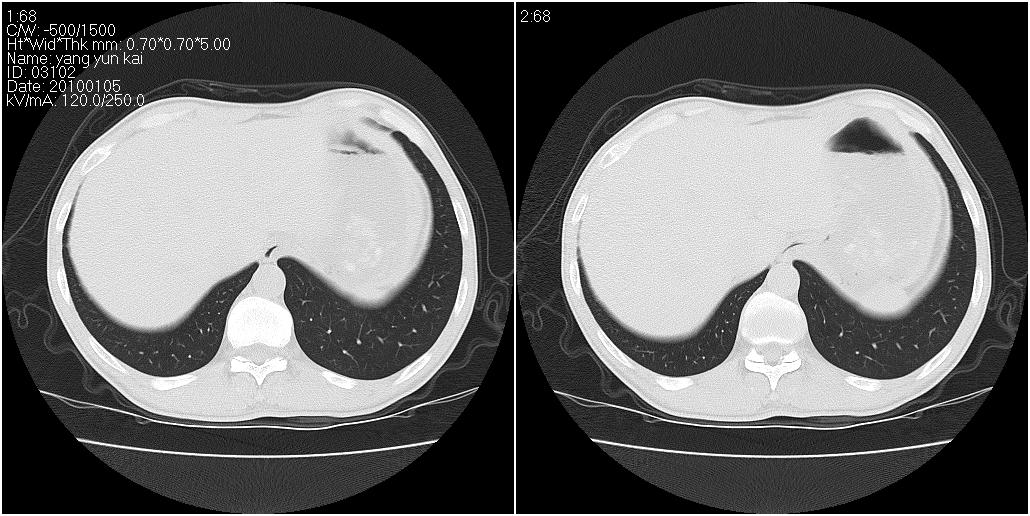

标题: CT23980:男性,47岁。近来咳痰、咳血,血沉增快(40左右),

男性,47岁。近来咳痰、咳血,血沉增快(40左右),痰中未检出结核杆菌。

两肺继发性肺结核并多发性结核球形成,部分病灶内空洞形成。